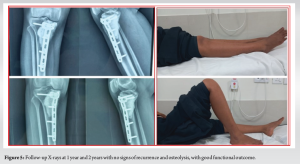

Intraoperative cultures revealed the growth of methicillin-sensitive staphylococcus aureus, sensitive to cefoxitin, gentamicin, cotrimoxazole, and doxycycline. The patient received 2 weeks of intravenous antibiotics followed by 4 weeks of oral antibiotics as per culture sensitivity, experiencing no postoperative wound complications and achieving a satisfactory functional outcome. Histopathology confirmed recurrence of GCTB, exhibiting characteristic multinucleated giant cells and neoplastic mononuclear cells surrounded by bone matrix. The patient was followed at regular intervals for 2 years with no signs of recurrence or infection (Fig. 5).